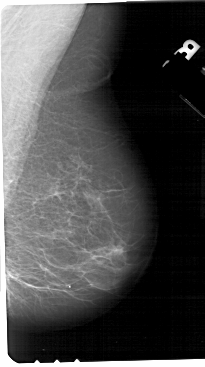

A_1651_1.RIGHT_MLO

RIGHT_MLO LINES 5491 PIXELS_PER_LINE 3061 BITS_PER_PIXEL 12 RESOLUTION 43.5 NON_OVERLAY